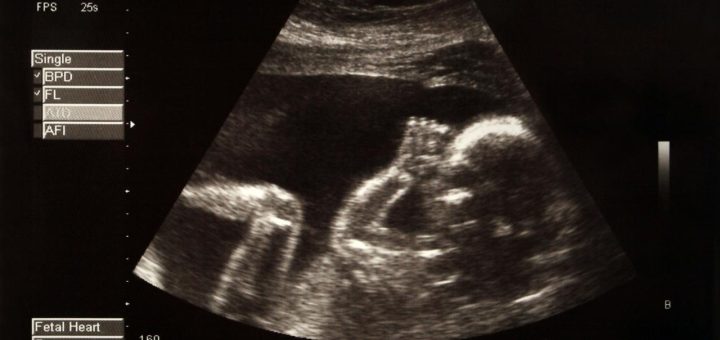

Category: Santé